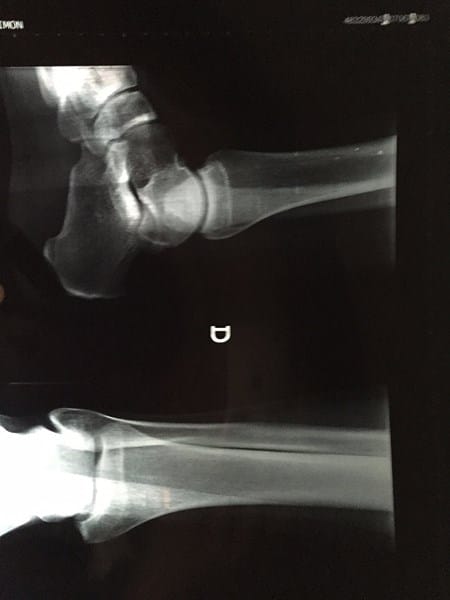

Segunda opinion rx tobillo derecho

Fui al traumatólogo y me dijo que podría tener osteocondritis, me mandó resonancia y radiografía, la resonancia la recojo el miercoles, que tal ve la radiografía, ¿podria ser?

Le adjunto la radiografía antes se me olvidó: